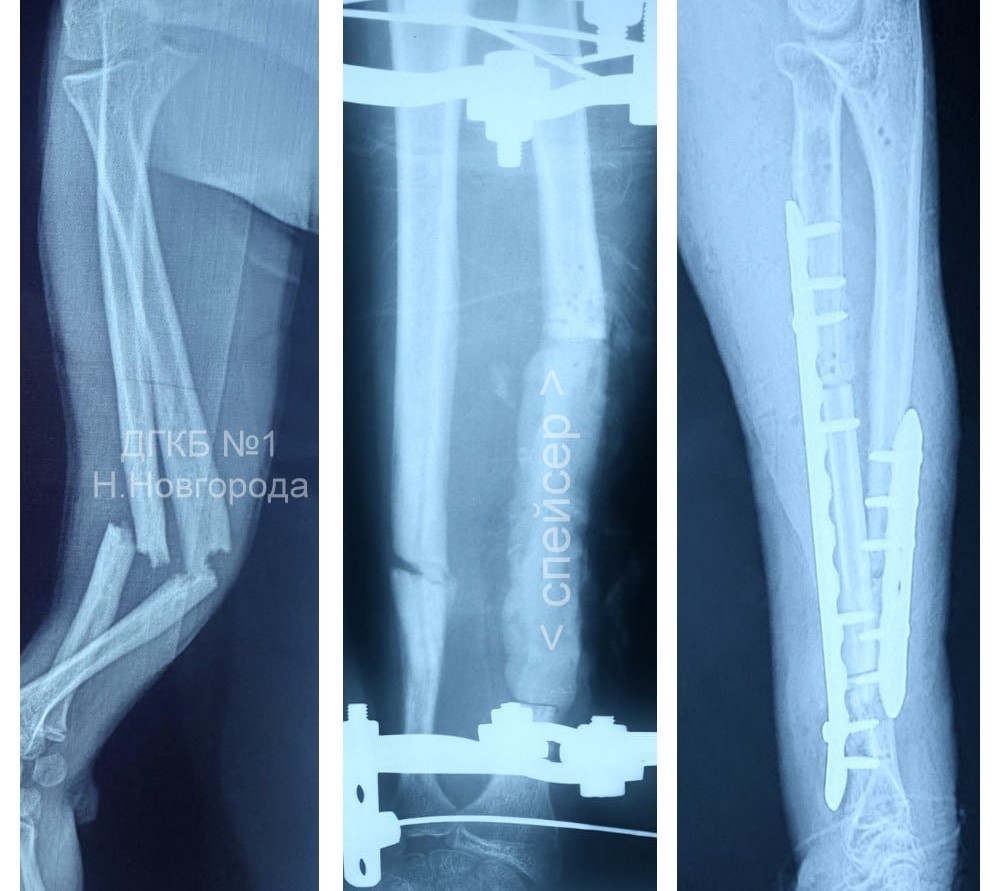

Несчастный случай произошёл во время каникул: подросток упал с небольшой высоты и получил закрытый перелом обеих костей левого предплечья. В зарубежной клинике ему провели операцию лишь на десятые сутки после травмы, что привело к развитию серьёзного осложнения — остеомиелита, гнойного воспаления костной ткани.

«На первом этапе лечения был зачищен гнойный очаг и удалено 9 сантиметров омертвевшей кости, на её место установили антимикробный спейсер с химиопрепаратами, а также выполнена переустановка аппарата Илизарова», — рассказал заведующий травматологическим отделением больницы Степан Секаев.

На втором этапе лечения врачи восстановили костную ткань с помощью аутотрансплантации: дефект заполнили фрагментом малоберцовой кости самого пациента, а повреждённые участки зафиксировали специальными пластинами. Руку подростка удалось не только спасти, но и полностью восстановить её функции. Сейчас пациент уже выписан из стационара и вернулся к привычному образу жизни.